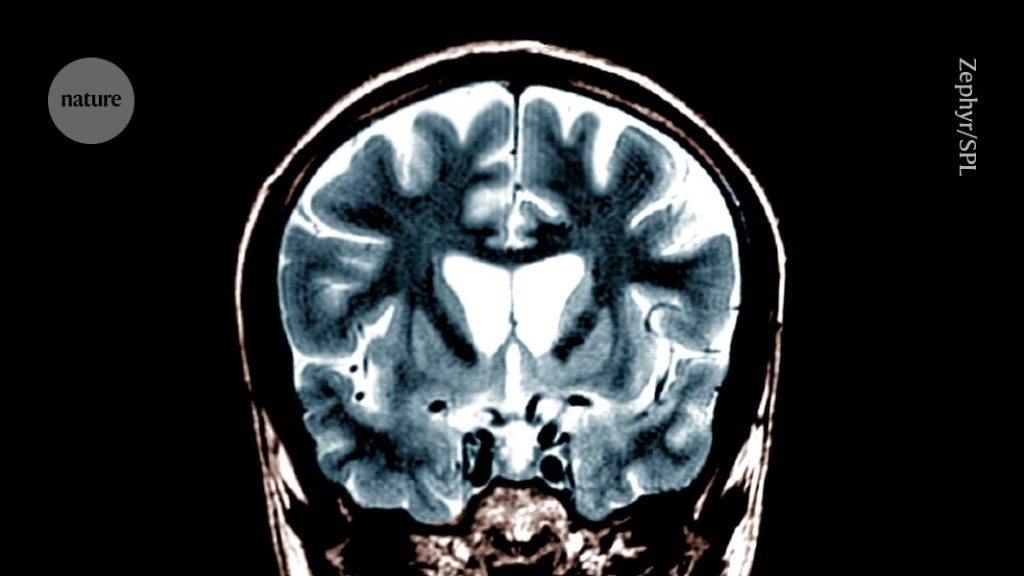

First use of gene therapy to treat Huntington’s disease

Significant Advancement in Huntington’s Disease Treatment A recent study indicates that a single gene therapy could significantly delay the progression of Huntington’s disease, potentially marking a pivotal moment for treatment options for this hereditary brain disorder. In a trial involving 29 participants at early stages of Huntington’s decline, those who received a high dose of […]